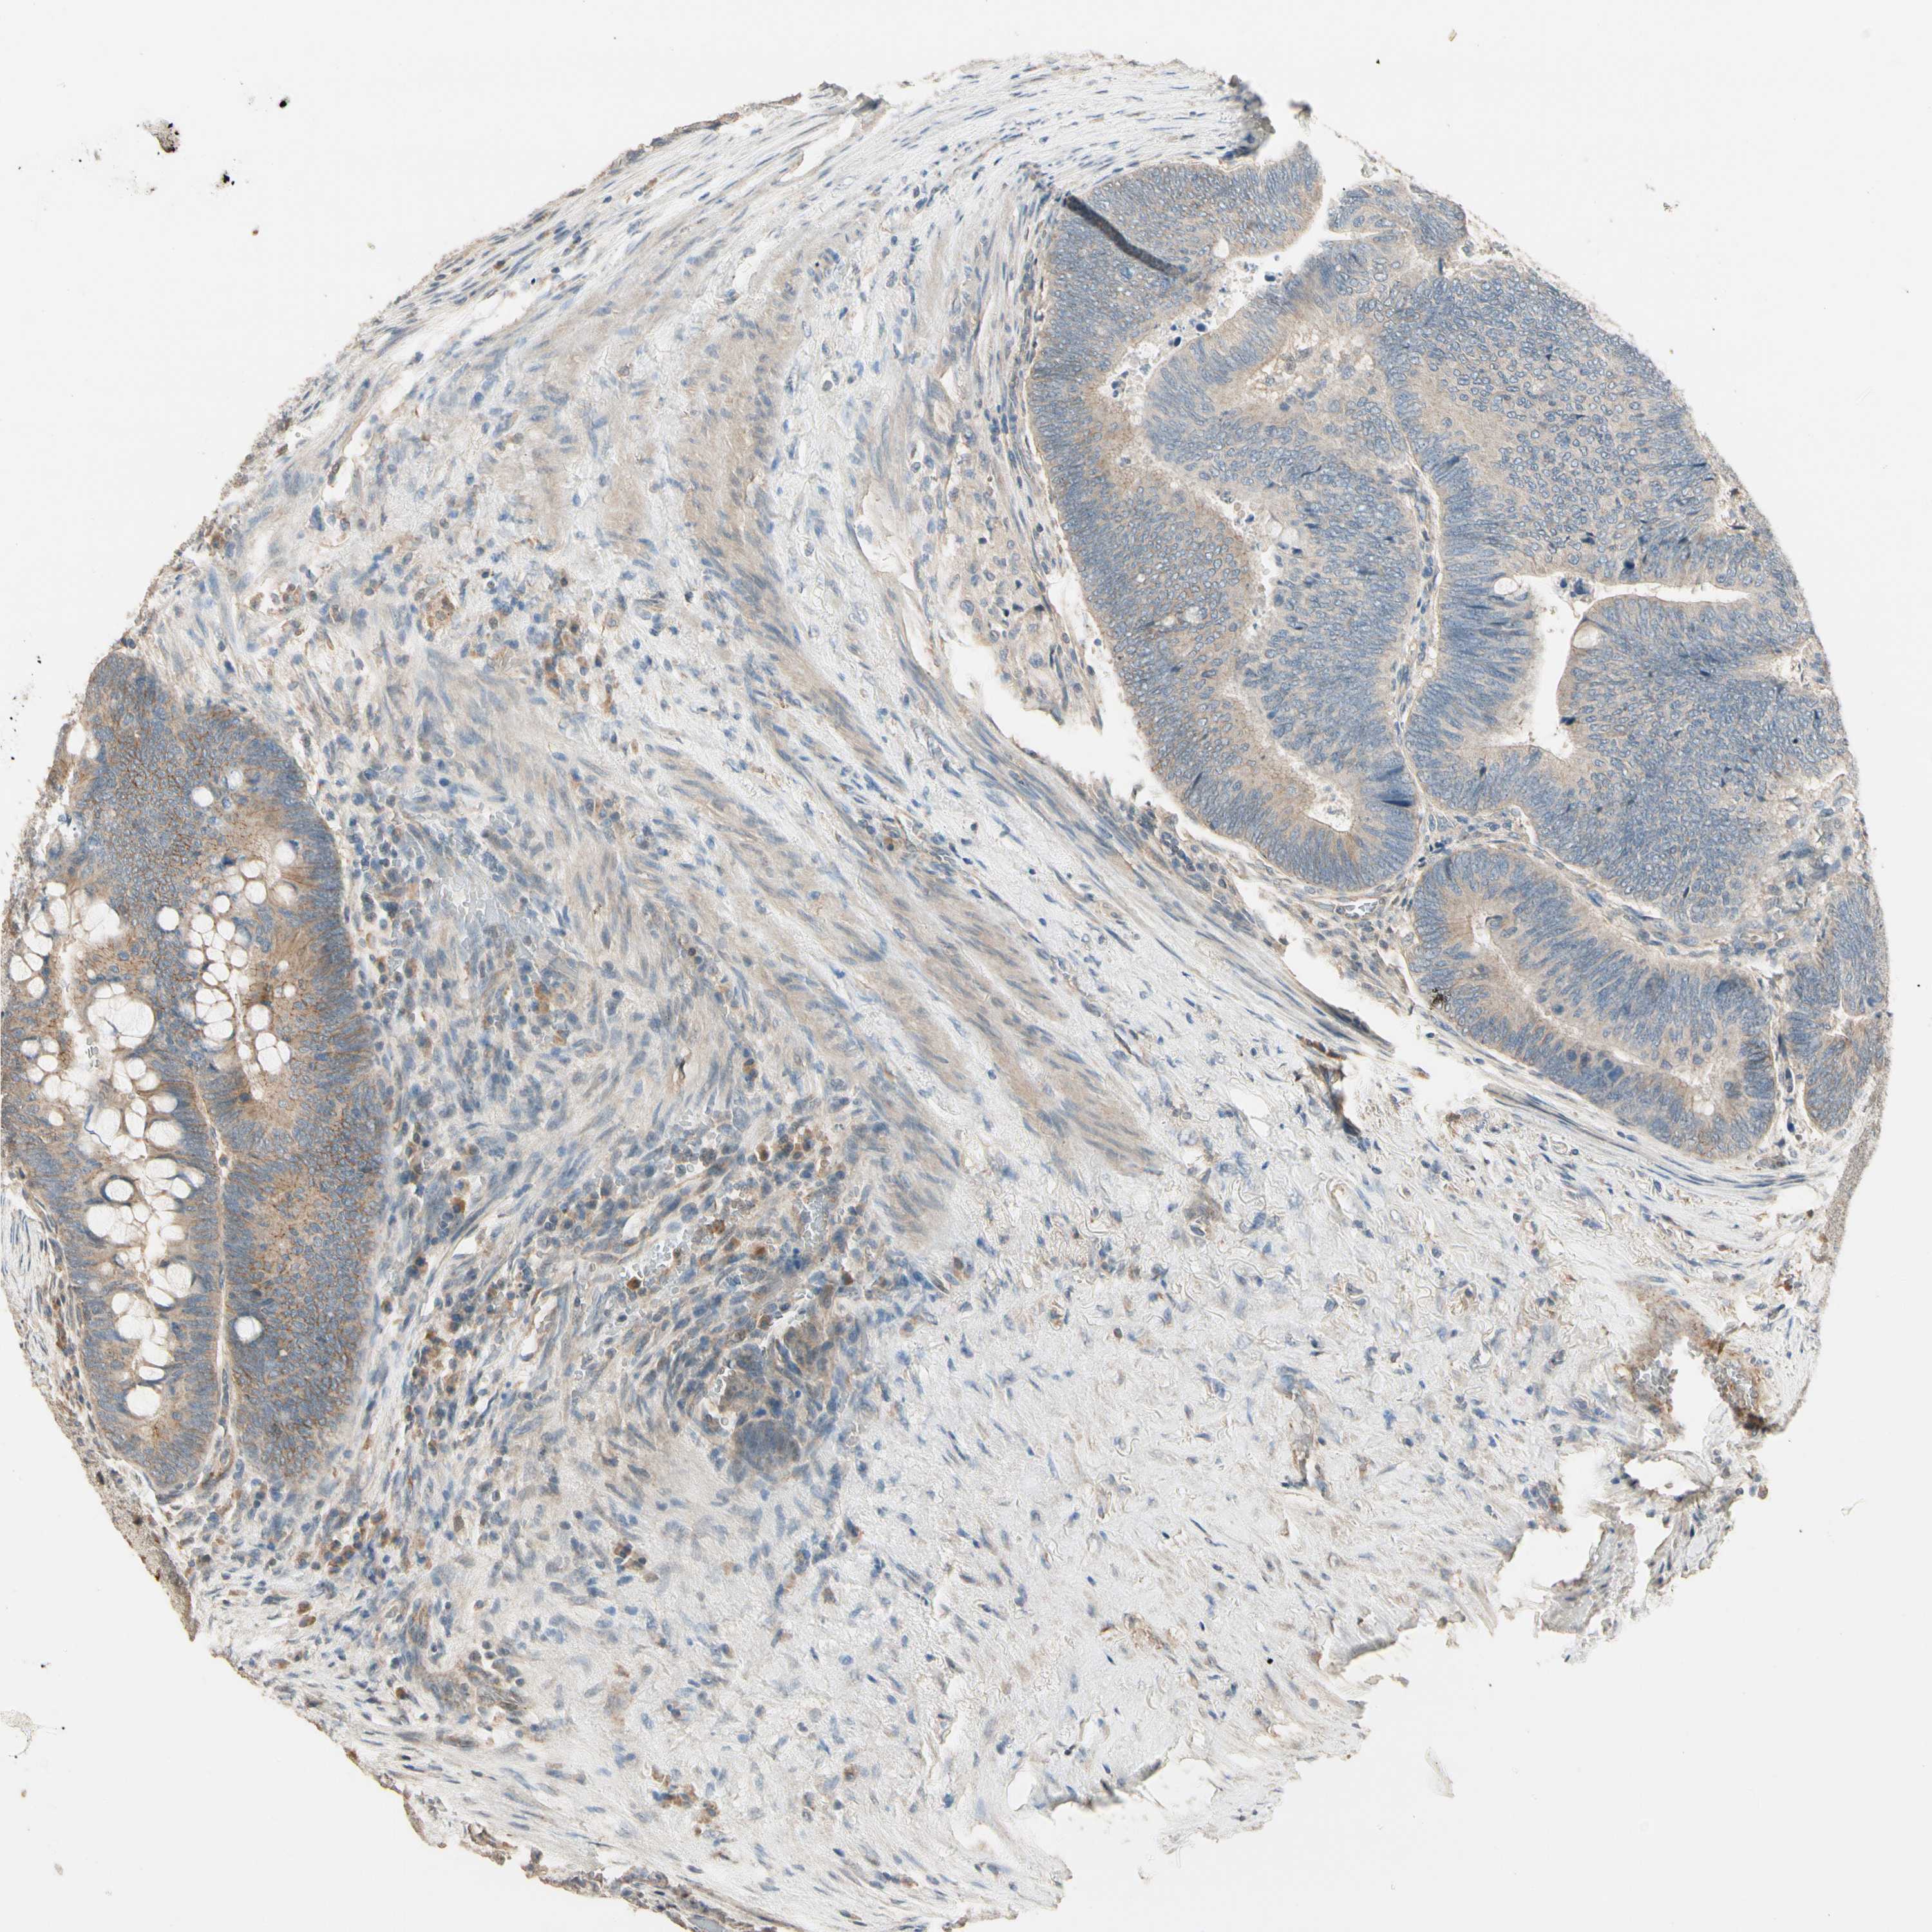

CANCER COLORECTAL CANCER Show tissue menu

Colorectal cancer

Colon adenocarcinoma